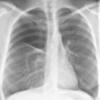

COPD

Date: 06/06/2004

Views: 14559